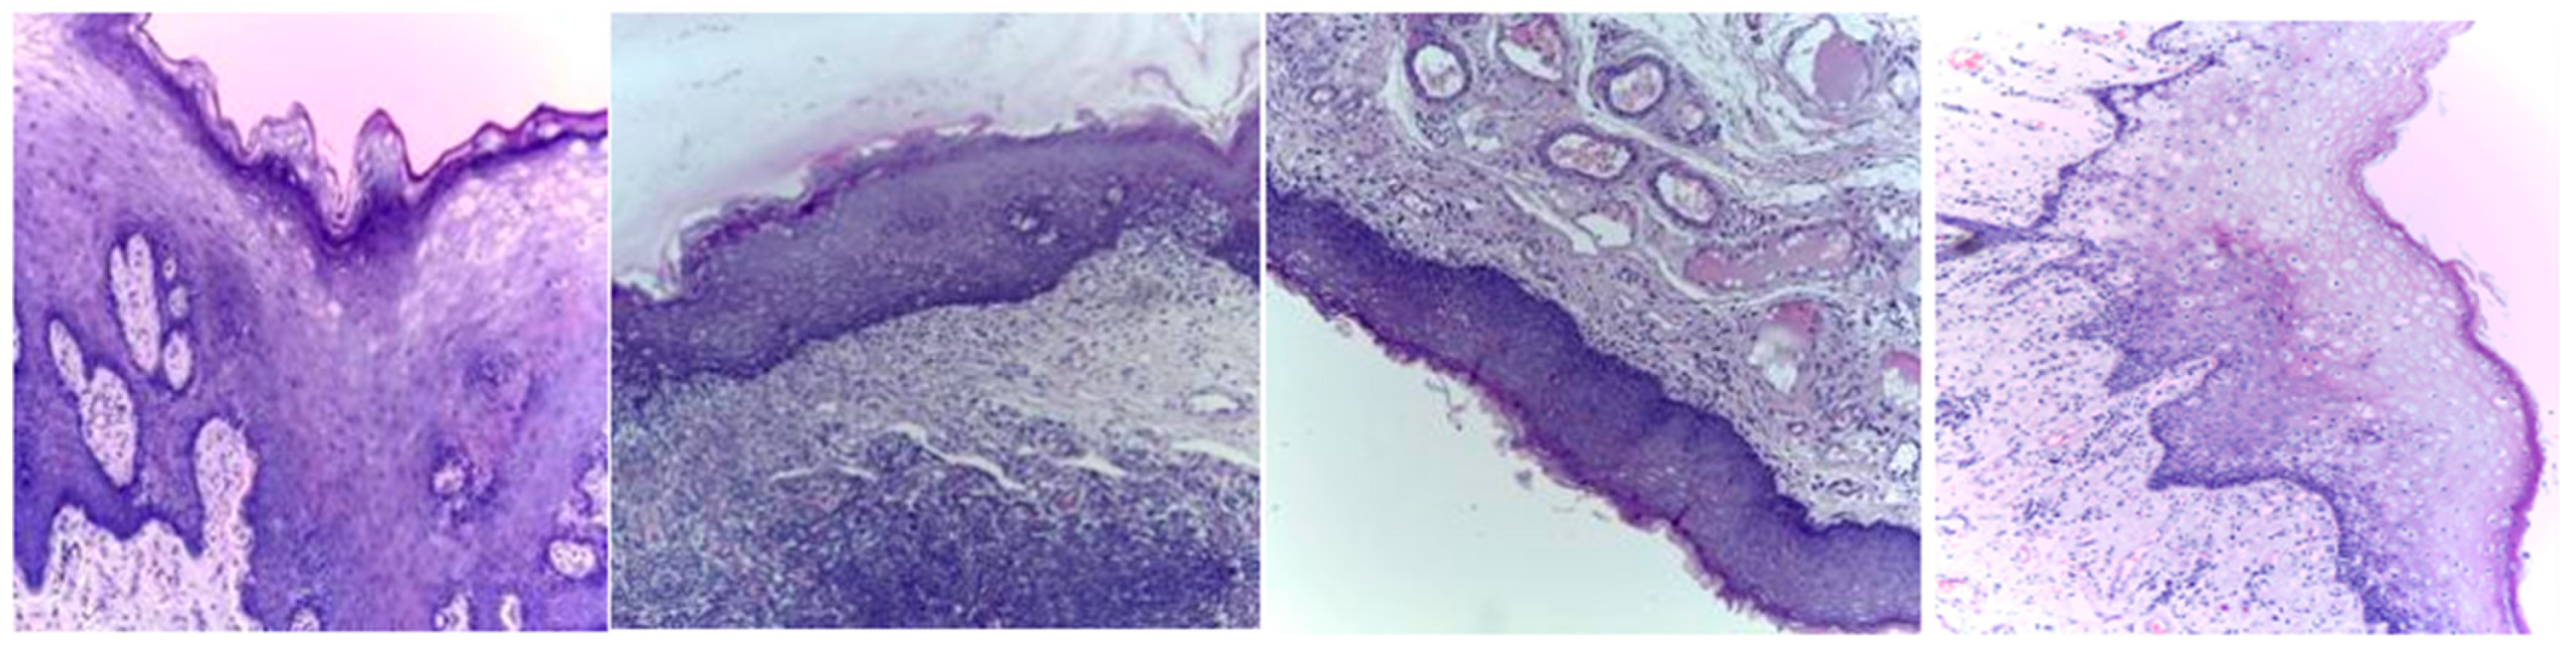

Three publicly available datasets comprising 2784 Normal and 3632 oral squamous cell carcinoma subjects are considered in this work. The first dataset was obtained from Kaggle [49], and it contains oral histopathological images at both the 100× and 400× zoom levels. The first dataset contains a total of 5192 images, and out of them, 2494 images belong to the Normal class and 2698 belong to OSCC class. The second and third datasets are obtained from the online repository built by Tabassum Yesmin Rahman et al. [50]. Oral histopathological images with zoom levels of 100× and 400× are present in the second and third datasets, respectively. A total of 89 normal images and 439 OSCC images are available in the second dataset, while 201 normal images and 495 OSCC images are available in the third dataset. Some of the sample oral histopathological images belonging to normal and OSCC classes are shown in Figure 1 and Figure 2, respectively.

Figure 1.

Sample oral histopathological images belonging to the Normal class.

Figure 2.

Sample oral histopathological images belonging to OSCC class.